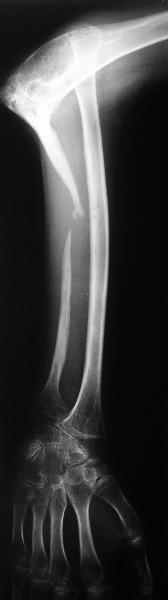

Молодой человек 2-3 года назад наблюдался по поводу прогрессирующего остеолиза правой локтевой кости. Морфологически - гемангиома, возможно, ангиомоподобный остеолиз (болезнь Gorham-Stout). Получал лучевую терапию. К настоящему времени остеолиз не прогрессирует. Однако сформировался вывих лучевой кости. Рентгенограмма и функция - см. иллюстрации. Пациенту хотелось бы улучшить функцию. Что можно предложить? Постепенное вправление аппаратом, замещение дефекта локтевой кости, резекцию головки лучевой, оставить как есть, что-то еще?

У парня сносный объем движений, понятно, что не в суставе от которого уже ничего не осталось, а за счет движений лучевой головки в мягких тканях.

Судя по рентгенограмме, сформировался плечелоктевой артродез под углом около 90 градусов, поэтому тот объем движений, который выполняет пациент, обеспечивается за счет дефекта локтевой кости.